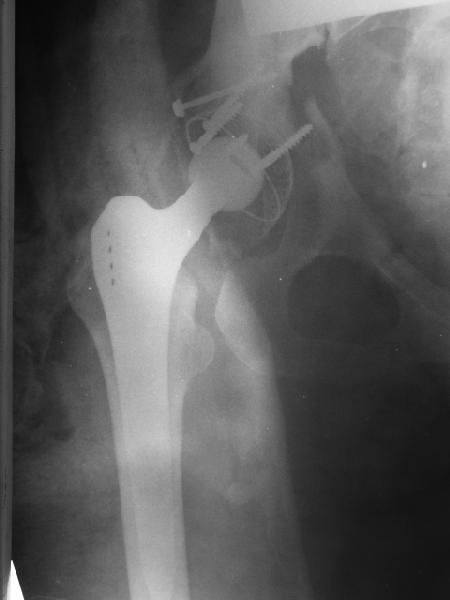

Получила поперечный перелом правой вертлужной впадины (снимок прилагается) с переломом ветвей лонной кости на другой стороне (inlet view также в приложении), а также поперечный перелом дистального метафиза бедра на этой же стороне. Что посоветуете в отношении протеза и впадины? Спасибо заранее.

A colleague of mine from another hospital requests opinion. A female 39 years old was operated ~1 year ago - right side THA for hypoplastic hip. Yesterday she was going to the hospital for THA of the second hip but got involved in a car accident. She admitted with right acetabular and left rami fractures (images attached). Also trasverse fracture of the right distal femur. Seeking your advice regarding the acetabular fracture. THX!